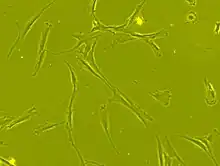

Morphologie

Les CSM ont un corps cellulaire petit, avec quelques éléments cellulaires longs et minces.

Ce corps cellulaire contient un gros noyau rond avec un nucléole proéminent, entouré de fines particules de chromatine dispersées, donnant au noyau une apparence claire.

Le reste du corps cellulaire contient une petite quantité d'appareils de Golgi, un réticulum endoplasmique rugueux, des mitochondries et des polyribosomes.

Ces cellules, longues et minces, sont largement dispersées, et la matrice extracellulaire adjacente est peuplée de quelques fibrilles réticulaires mais dépourvue d’autre types de fibrilles de collagène[39],[36].

La Société internationale de thérapie cellulaire (ISCT) a proposé des critères de définition les CSM = une cellule peut être classée MSC si elle présente des propriétés d'adhérence plastique dans des conditions de culture normales et si elle a une morphologie de type fibroblaste.